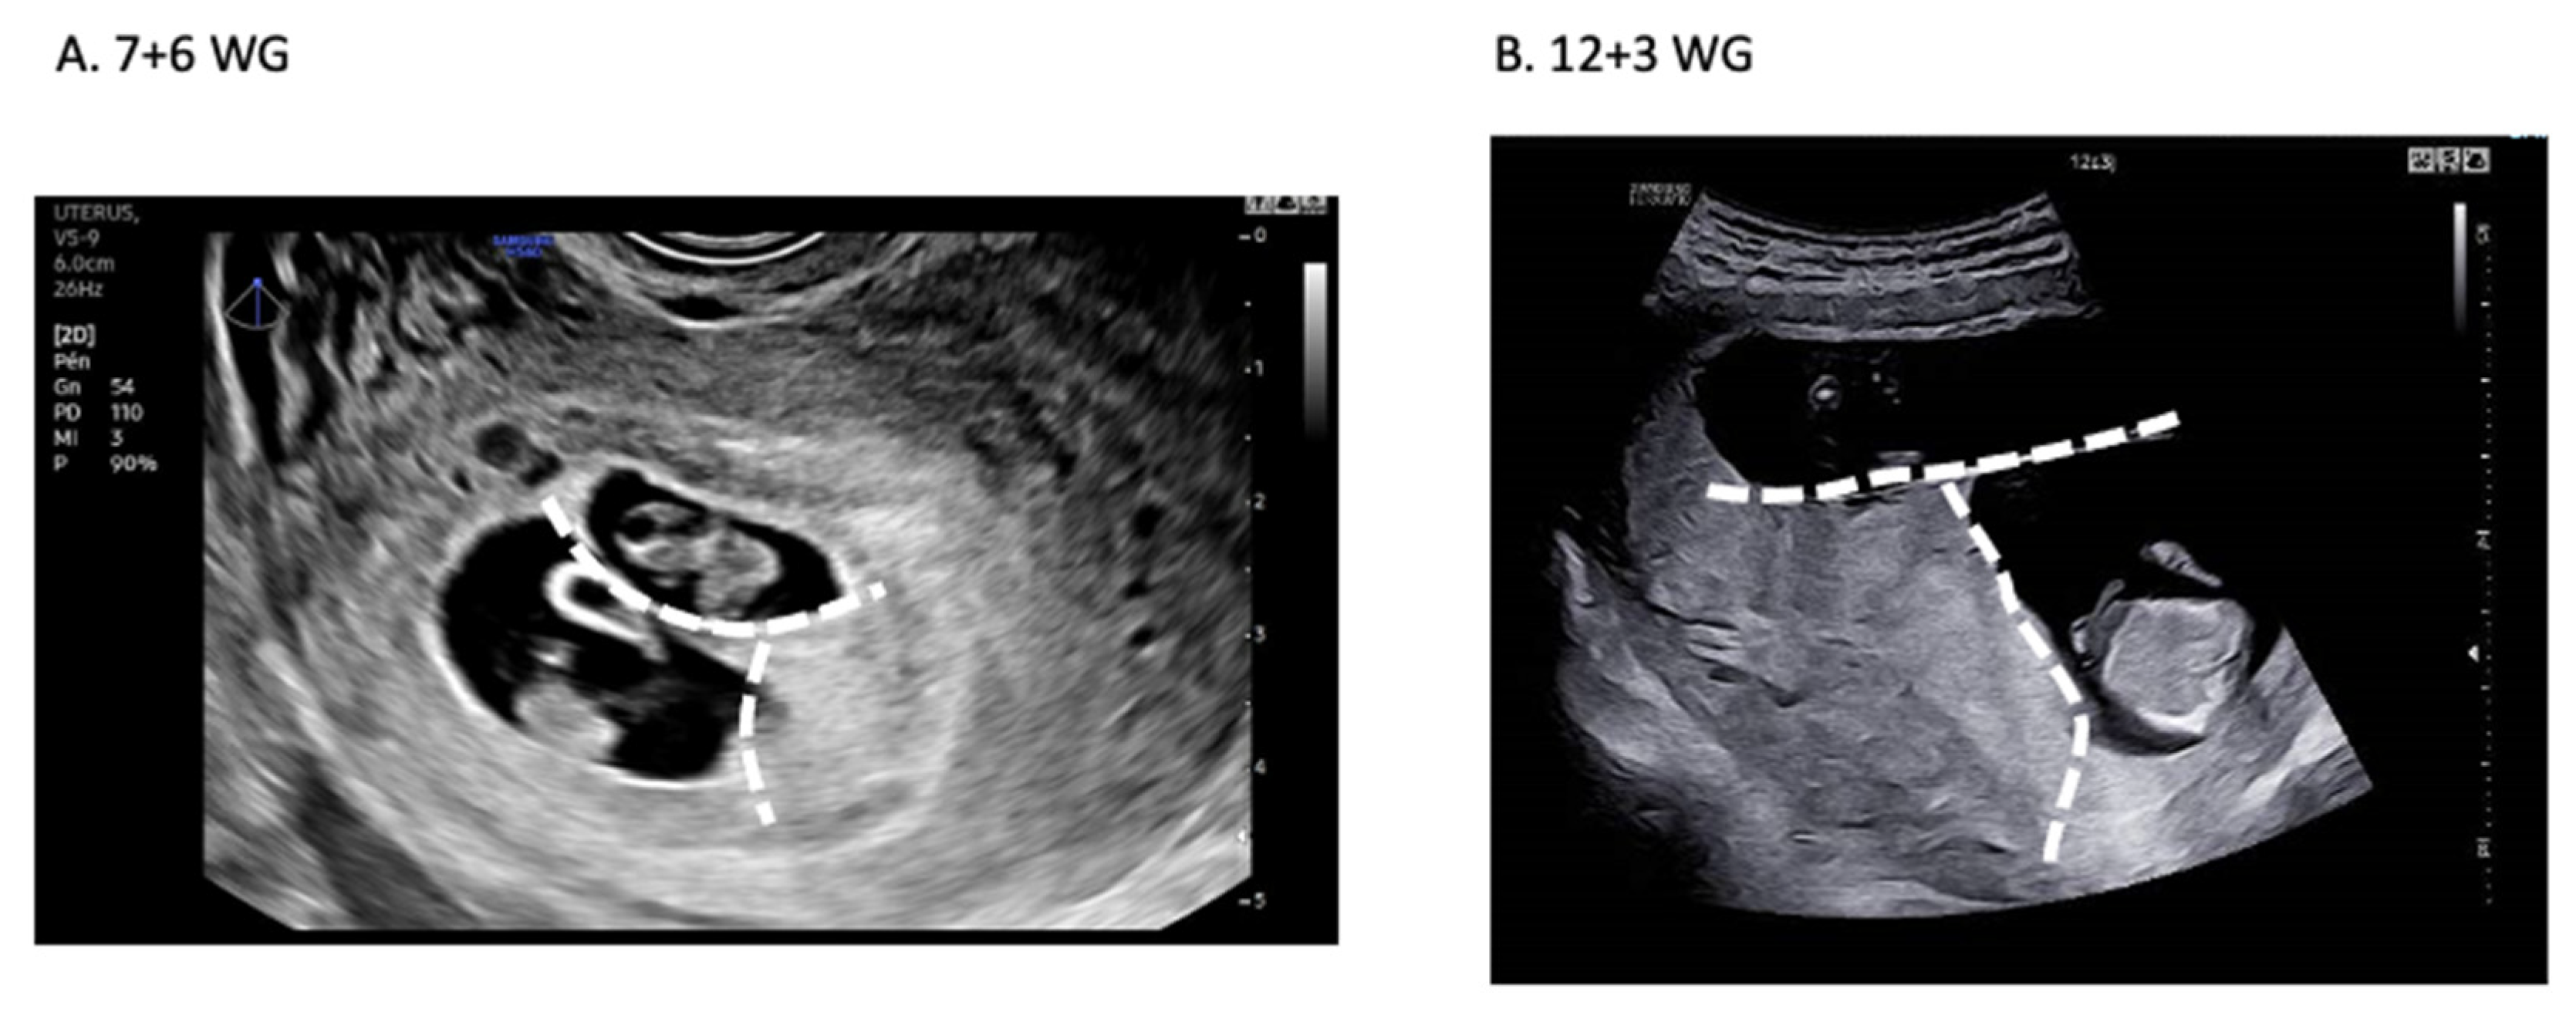

- Pregnancy

4.5. Pregnancy